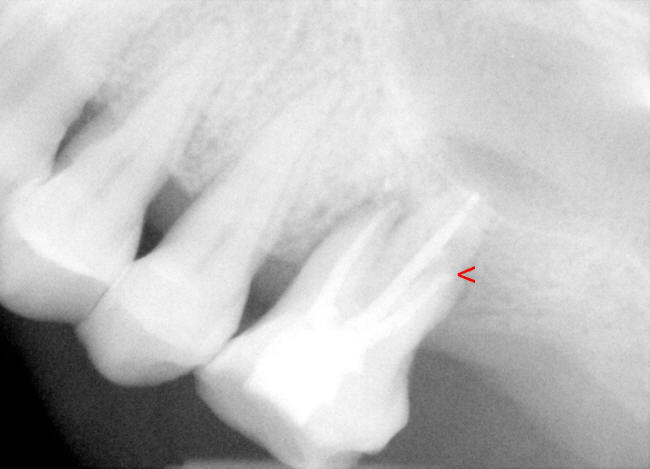

| 图一 术前根尖片左上6号牙根尖阴影阳性 | 图二 术前根尖片左上6号牙根尖阴影阳性 |

检查:面部对称,没有肿胀,没有牙关紧闭,口腔卫生尚可,多个修复物(补牙),左上7号牙缺失,左上6号没有蛀牙,牙龈退缩,4毫米牙周袋,轻度扣痛,没有窭道。根尖片(图一,图二)显示:左上6号牙骨质吸收,根尖有阴影。